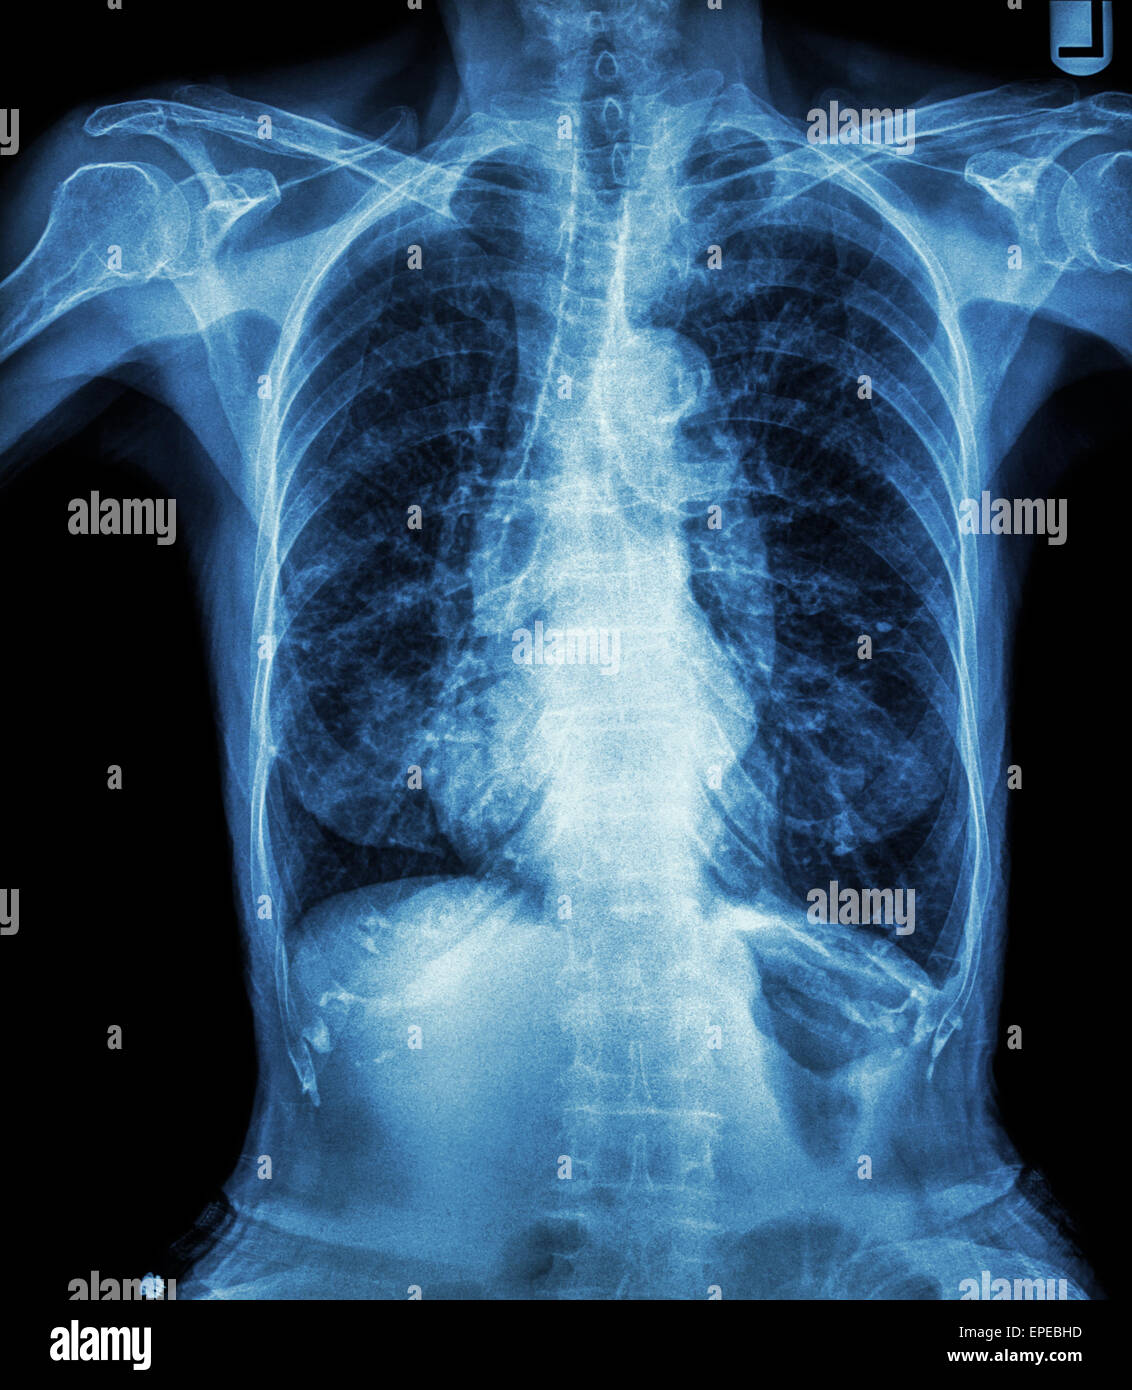

Tracheal Bronchus X Ray . In tracheal bronchus the right upper lobe is partially aerated by a bronchus that originates directly from the. Trachea, carina, bronchi and hilar. A tracheal bronchus (with some variations also known as a pig bronchus) is an anatomical variant where an accessory bronchus originates directly from the supracarinal. Tracheal calcification, or tracheobronchial calcification, is a benign radiological finding of the middle aged and elderly and is usually of no clinical significance. However, most cases are incidental findings on bronchoscopy. This is the result of massive lymphadenopathy in.

However, most cases are incidental findings on bronchoscopy. This is the result of massive lymphadenopathy in. In tracheal bronchus the right upper lobe is partially aerated by a bronchus that originates directly from the. A tracheal bronchus (with some variations also known as a pig bronchus) is an anatomical variant where an accessory bronchus originates directly from the supracarinal. Tracheal calcification, or tracheobronchial calcification, is a benign radiological finding of the middle aged and elderly and is usually of no clinical significance. Trachea, carina, bronchi and hilar.

Tracheal Bronchus X Ray However, most cases are incidental findings on bronchoscopy. In tracheal bronchus the right upper lobe is partially aerated by a bronchus that originates directly from the. A tracheal bronchus (with some variations also known as a pig bronchus) is an anatomical variant where an accessory bronchus originates directly from the supracarinal. Tracheal calcification, or tracheobronchial calcification, is a benign radiological finding of the middle aged and elderly and is usually of no clinical significance. Trachea, carina, bronchi and hilar. This is the result of massive lymphadenopathy in. However, most cases are incidental findings on bronchoscopy.